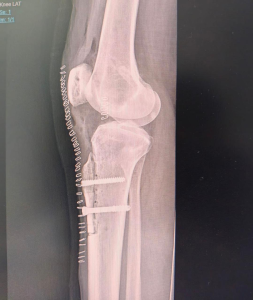

AP View (Front View)

Postoperative X-rays showing screw fixation and successful bone realignment after kneecap stabilisation surgery